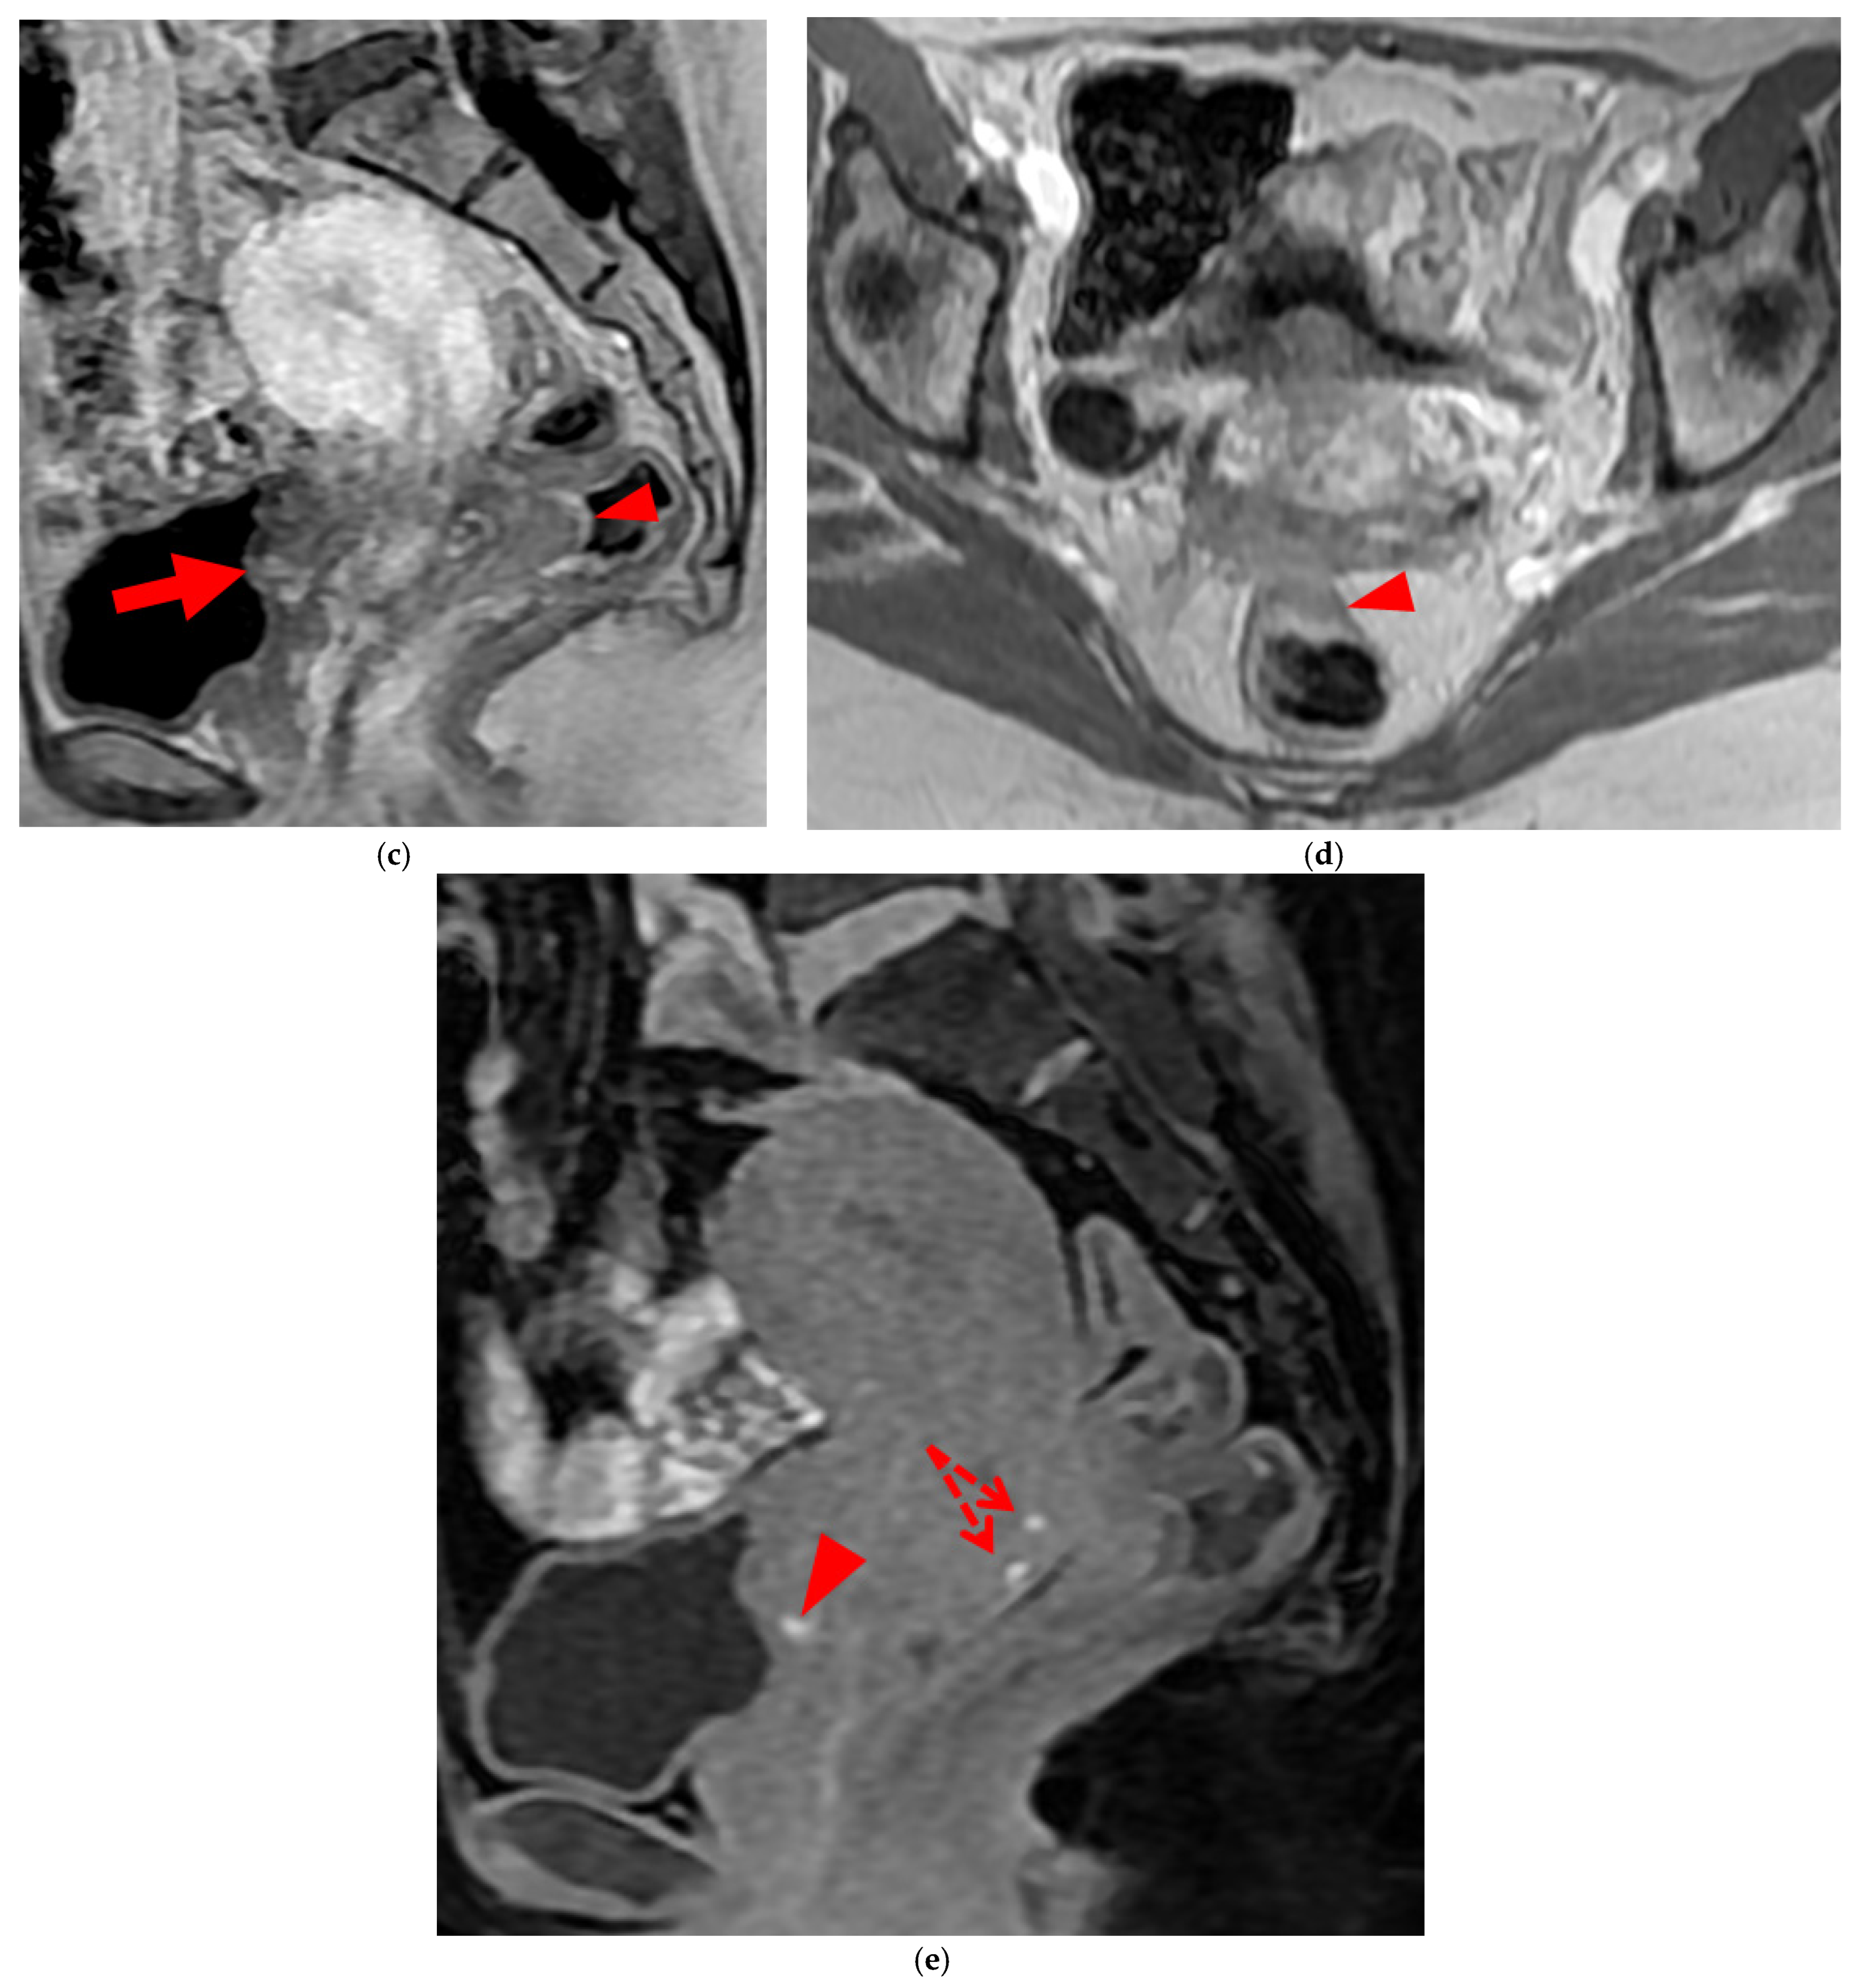

A type 3 USL appears as thickened (i.e., >2 mm), and can be classified either as type 3A (PPV = 75%; FPR = 25%) or as type 3B (PPV = 80%; FPR = 20%).

A type 3A USL (Figure 3) maintains a smooth appearance with regular margins and often retains a tapering shape despite its thickening.

A type 3B USL (Figure 4), in addition to being thickened, has a notched surface with slightly irregular margins, or a caliber disparity with focal thickening, or appears “stiffened”, which means it loses its curvilinearity to exhibit a steep vertical orientation in the sagittal plane or a “bowstringing” of the USL in the sagittal or axial planes. Occasionally, a USL might appear thin but “stiffened”, which would upgrade it from a type 2 to a type 3B.

Figure 3. Pelvic MRI scans of three patients with thick (>2 mm), smooth, and regular USLs (HTD type 3A). (a) Sagittal T2WI: a thick (2.8 mm), smooth, tapering-shaped left USL (arrowhead). (b) Axial T2WI: regularly thickened (3 mm) right USL with a smooth surface (arrowhead). (c) Axial T2WI: regularly thickened (4.1 mm) right USL with a smooth surface (arrowheads).